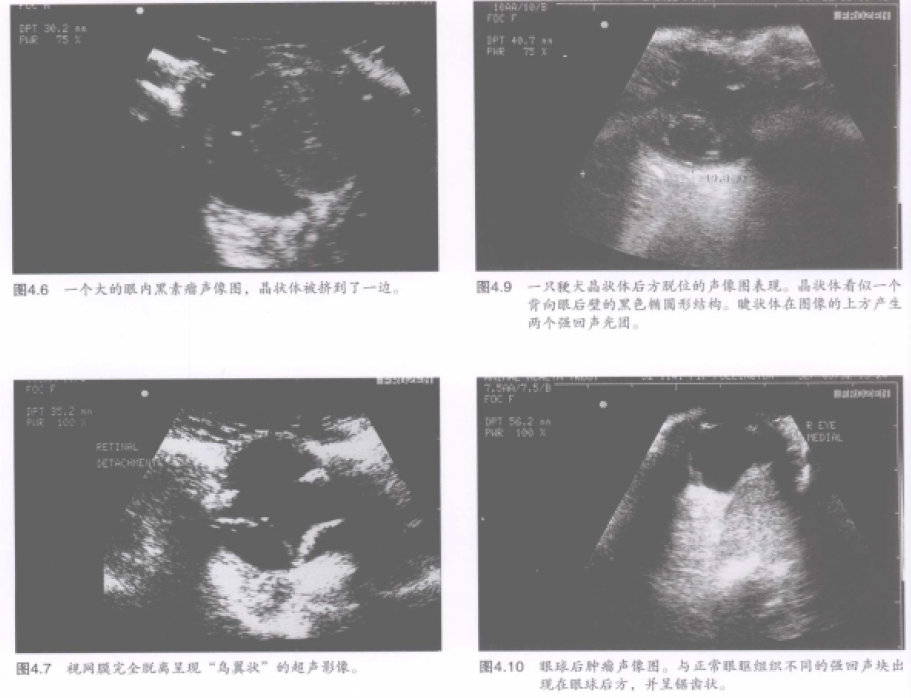

超声常用来检查眼内肿块,尽管它既不能鉴别其组织类型也不能区分是血肿还是肿瘤(图4.6)。游离的血液呈液性暗区,其中的碎片呈现为无结构的回声增强影,通常随着眼球运动于周围回荡。视网膜脱离不难鉴别,完全脱离的视网膜在图像上呈现“鸟翼状”,因其还残留在视网膜锯齿缘和视神经乳头上(图4.7)。其他线性回声可能是由玻璃体视网膜牵引和眼内异物所产生。有些眼内异物可能产生特异性回声结构和声影(图48)。晶状体脱位容易鉴别,特别是晶状体出现混浊(在这种病例中出现回声结构)或是被眼内出血包围(这时表现为无回声的“充盈缺损”)的情况下(图49)。